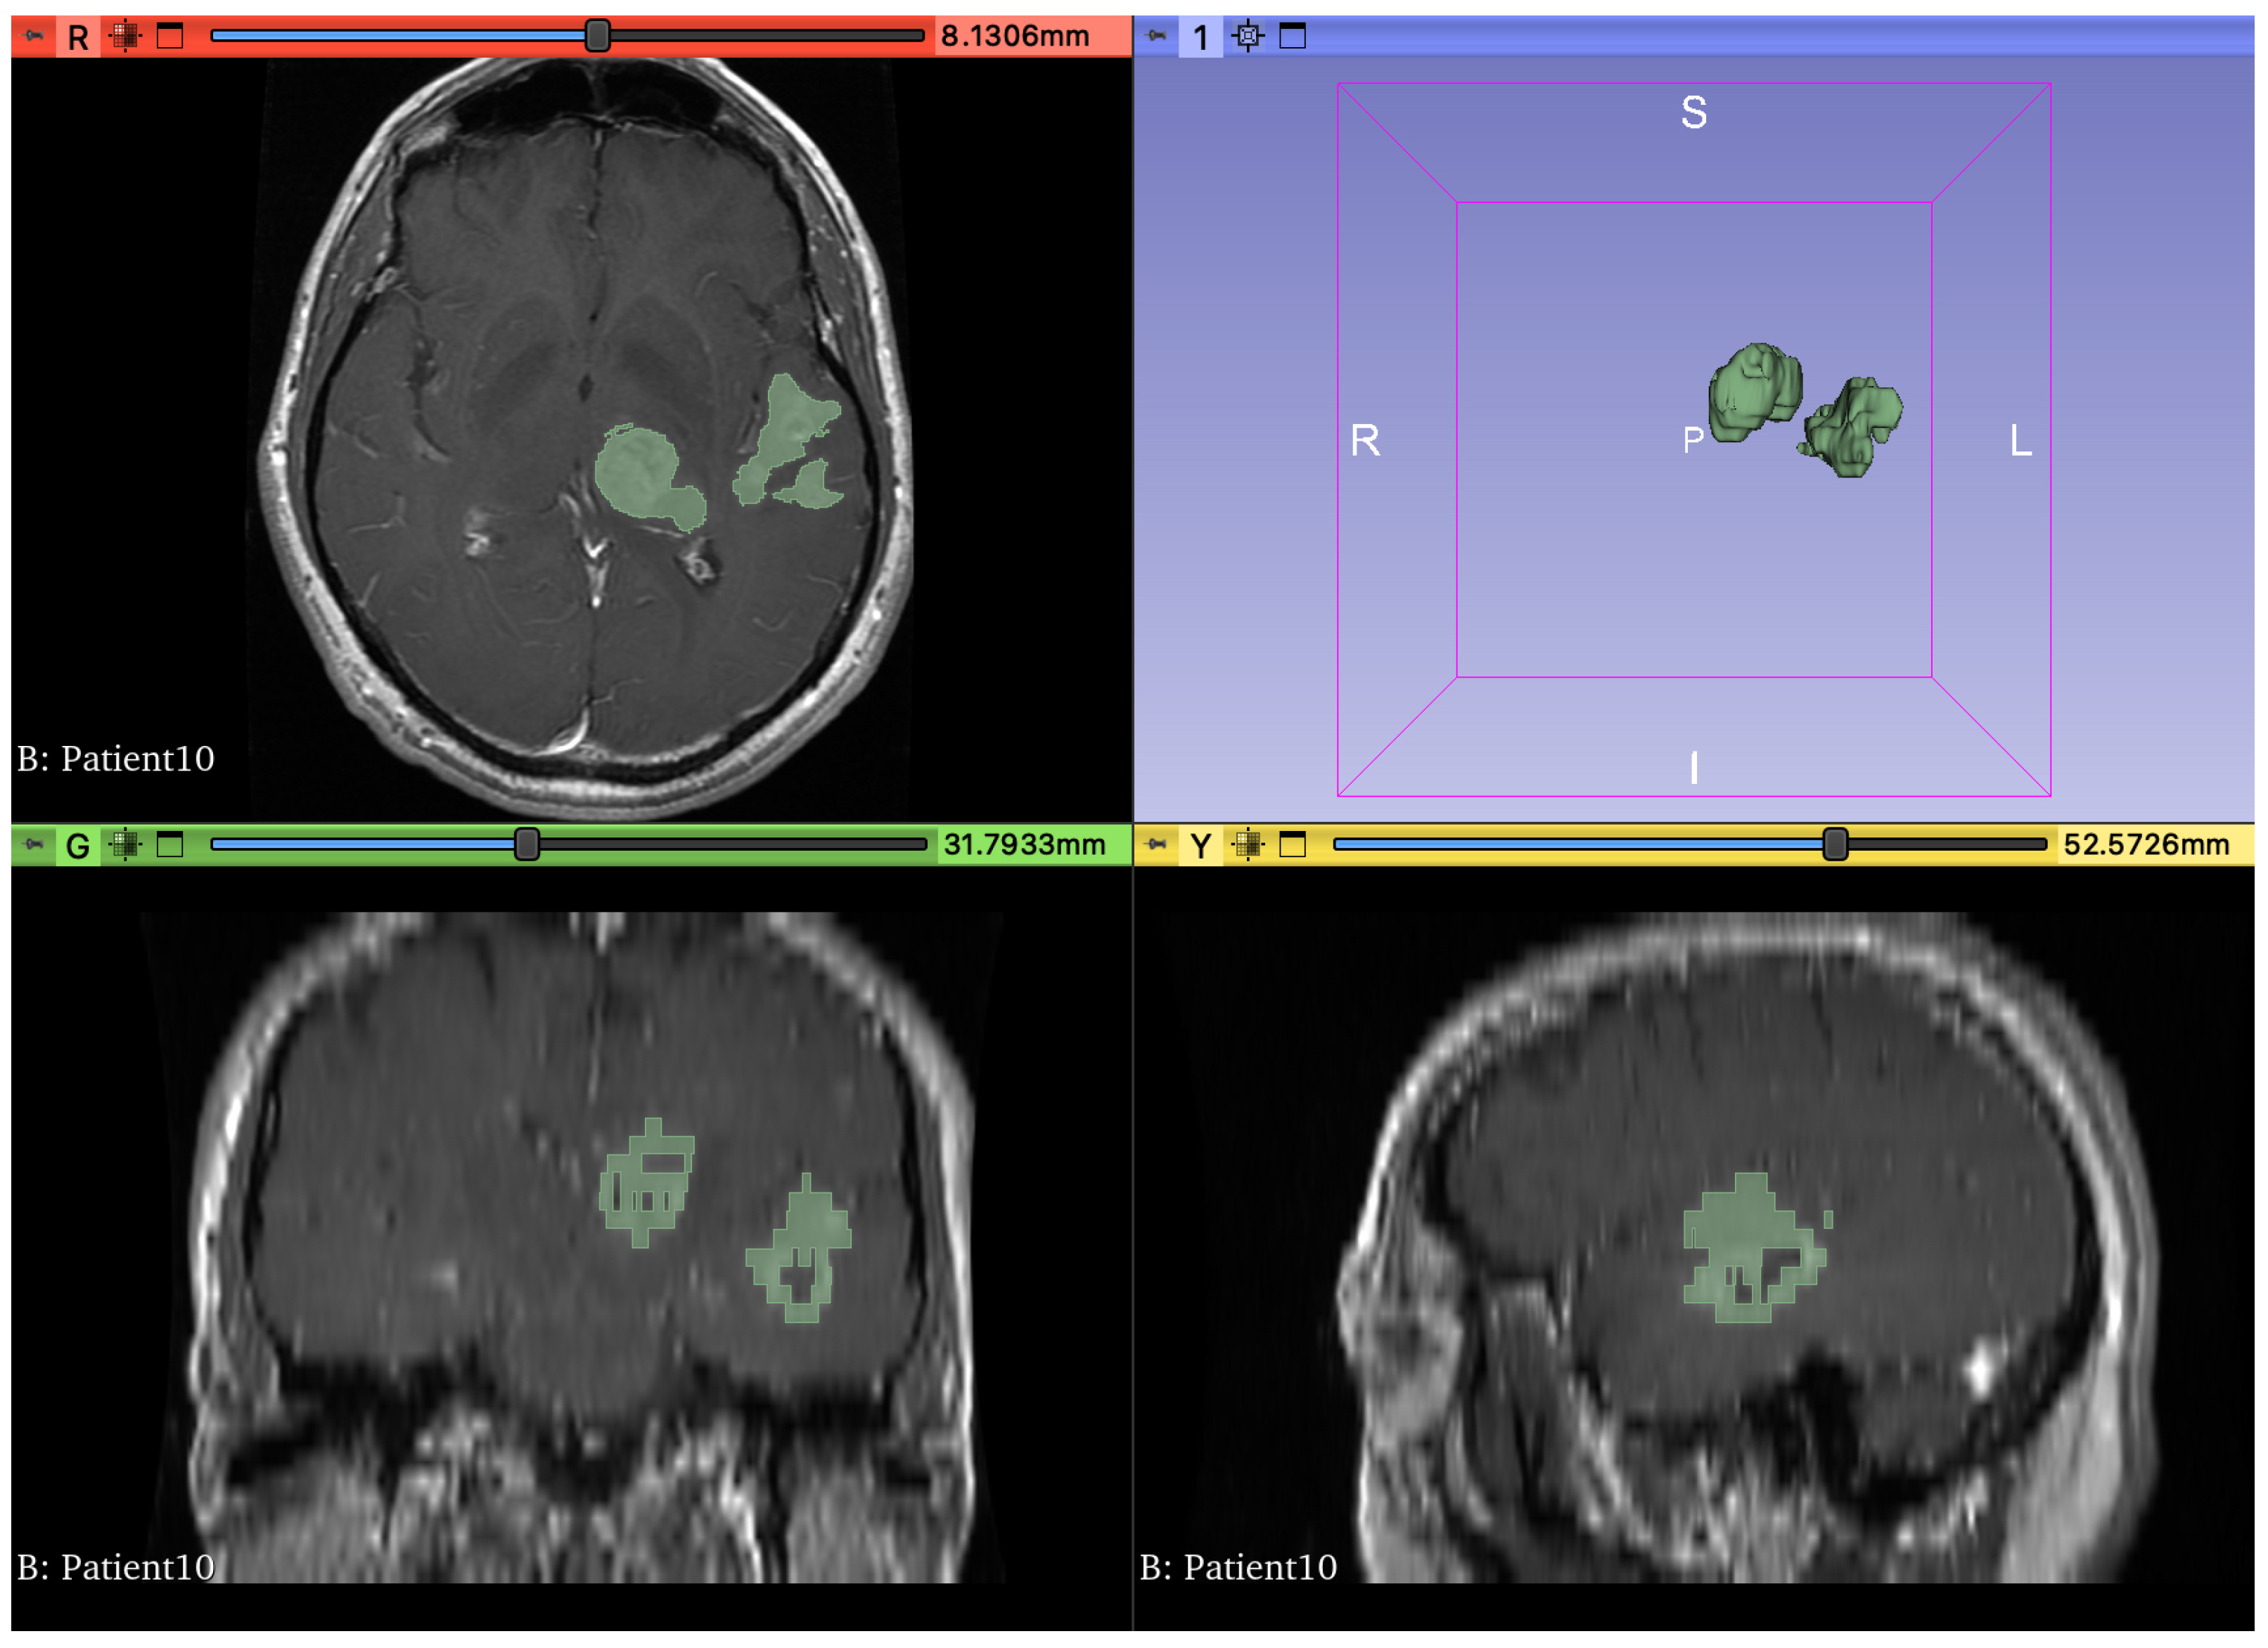

2. Method Description

3. Database Description

4. Experimental Assessment